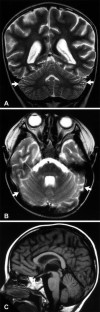

We describe MRI of the brain in 19 patients with ataxia-telangiectasia (AT) and correlate the appearances with the degree of neurologic deficit. We examined 10 male and nine female patients; 17 were aged between 2 and 12 years (mean 8 years) but a woman and her brother were 35 and 38 years old, and had a variant of AT. Ataxia was the first recognized sign of the disease in every patient. We detected the following patterns of cerebellar atrophy: in the youngest patient, aged 2 years, the study was normal; in the five next youngest patients 3–7 years of age, the lateral cerebellum and superior vermis showed the earliest changes of atrophy; and all but one of the other patients had moderate to marked diffuse atrophy of vermis and cerebellar hemispheres. There were 12 patients aged 9 years and above; one, who was normal, was 9 years old. The five patients who at the time of examination were unable to walk all had diffuse atrophy involving both vermis and cerebellar hemispheres.